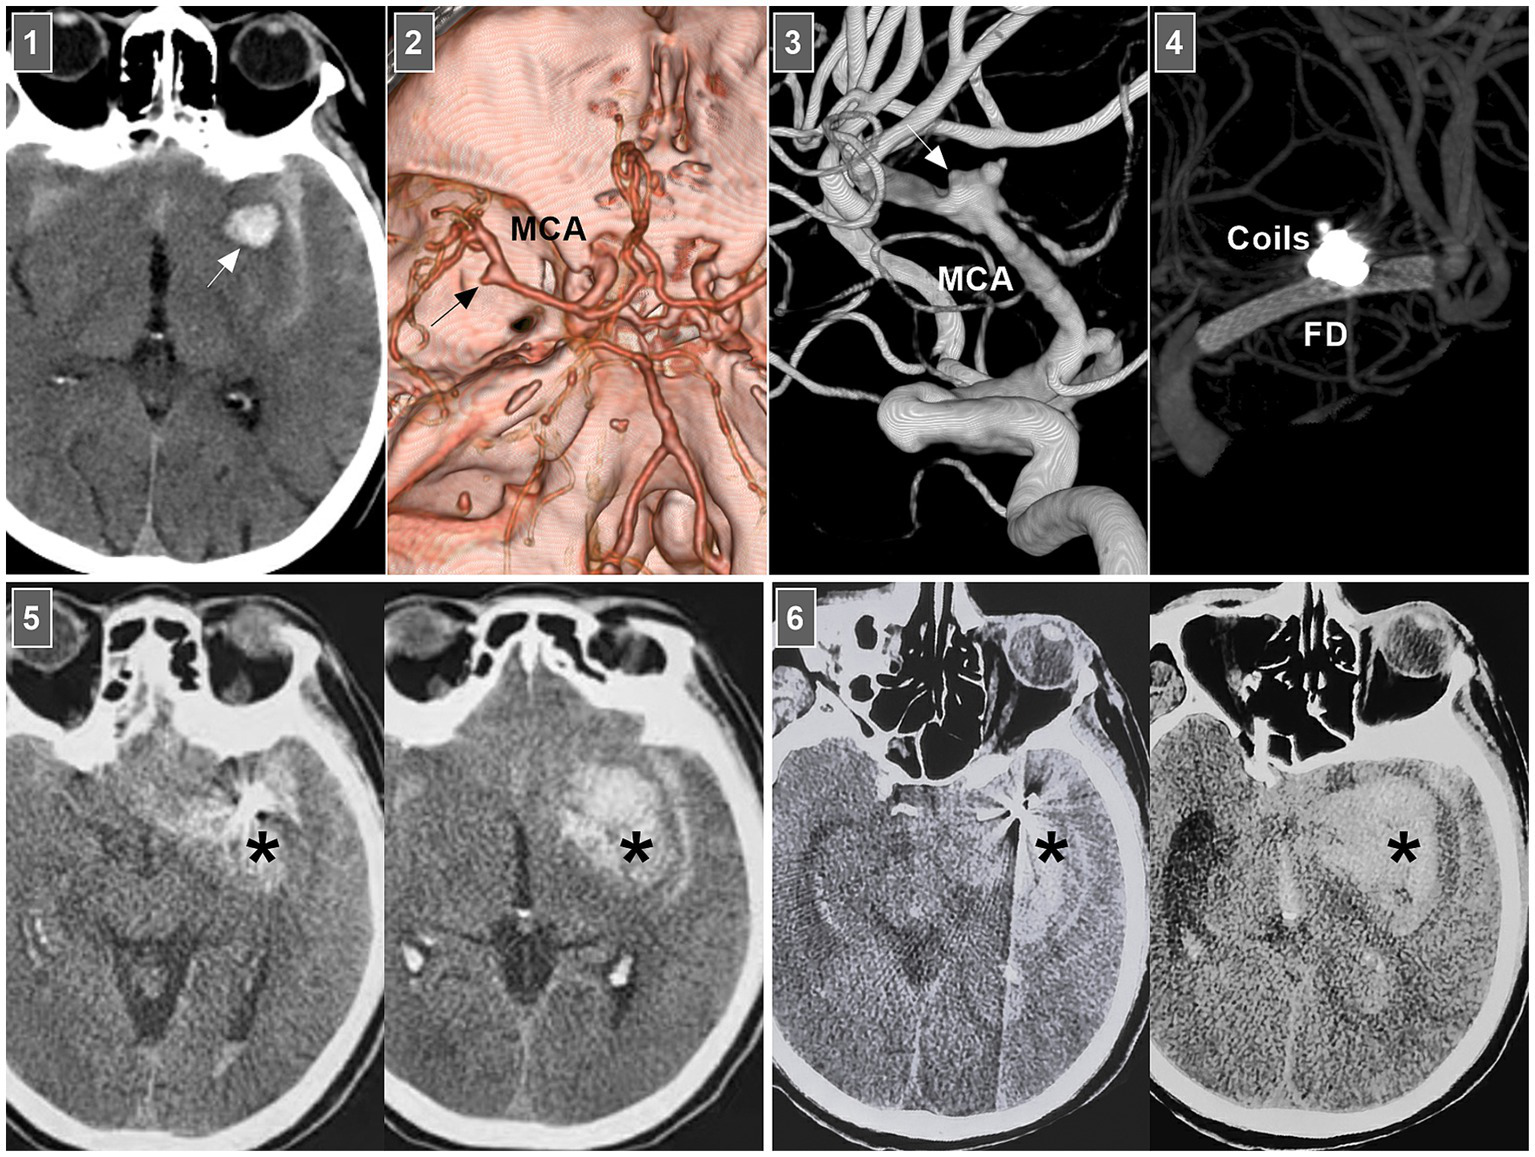

In selective hemorrhagic MCA dissection without severe stenosis, stent-assisted coiling may be effective (55, 56). For acute dissection, the rupture site is very fragile, and excessive coil packing should be avoided due to the risk of rupture (Figure 6). FDs can decrease blood flow into the rupture site. However, for stenotic MCAs, delivering the FD through a thick microcatheter is often difficult. For hemorrhagic MCA dissection with severe stenosis, conservative treatment had to be the last resort (Figure 7A).

Figure 6

Rebleeding after EVT of an MCA dissection. Panel 1: CT showing subarachnoid hemorrhage and parenchymal hematoma (arrow). Panel 2: CT angiography showing a left MCA trunk aneurysm (arrow). Panel 3: DSA showing that the aneurysm (arrow) was an MCA trunk dissection involving the origin of lenticulostriate artery. Panel 4: Vaso-reconstructive image showing that MCA dissection was coiled by FD assistance. Panel 5: Postoperative 1-h CT images showing increased hemorrhage (asterisks), indicating the MCA dissection reruptured. Panel 6: Postoperative 3-h CT images showing the bleeding (asterisks) continued to increase, the patient fell into coma. CT, computed tomography; DSA, digital subtraction angiography; EVT, endovascular treatment; FD, flow diverter; MCA, middle cerebral artery.

Chronic MCA dissections can present with fusiform or sidewall aneurysmal dilatation. For M1 dissections, FD deployment to reconstruct the M1 segment is an option (Figures 7B,C). For M2 dissections, reconstructive EVT is recommended (Figures 7D,E). However, complications associated with FD deployment must be considered (Figures 6, 8A). If the dissections of the M2 segment of the inferior trunk are giant with thrombi, the distal MCA may experience ischemic preconditioning, and deconstructive EVT is acceptable (57). PAO for M3–M4 dissections can be performed because of adequate leptomeningeal and pial collaterals from the anterior cerebral artery (ACA) and posterior cerebral artery (PCA) (57). In addition, for flow-related distal MCA dissections, deconstructive EVT can be aggressively performed. However, if branches are supplied to important functional areas, such as the central sulcal artery, precentral sulcal artery and postcentral sulcal artery, PAO should be performed cautiously (Figure 8B) (58).

Figure 8

Complication from EVT for MCA dissections. (A) Panel 1: DSA showing a sidewall dissection at M1–M2 junction (arrow). Panel 2: Roadmap image (left panel) and DSA (right panel) showing the dissection was covered by FD. Panel 3: Six-month follow-up DSA showing that the dissection was cured and there was a stenosis of M2 (arrow). (B) Panel 1: DSA (left panel) and microcatheter angiography (right panel) showing a small dissection of M3 (arrows). Panel 2: DSA showing the dissection was embolized by casting liquid embolic agent. Panel 3: Postoperative magnetic resonance image showing that the acute infarction of parietal lobe (frame). DSA, digital subtraction angiography; EVT, endovascular treatment; FD, flow diverter; MCA, middle cerebral artery; M1, first segment of MCA; M2, second segment of MCA; M3, third segment of MCA.